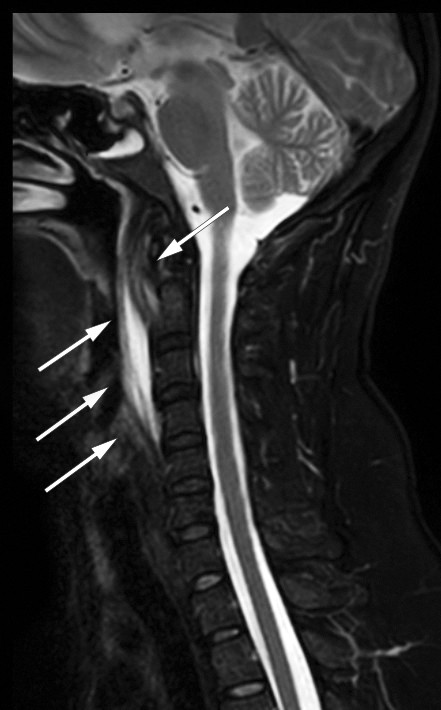

Det ble supplert med MR-undersøkelse av cervikalcolumna, som bekreftet væske i det retrofaryngeale rommet og ødem i bløtvevet prevertebralt, men utelukket spondylodiskitt (figur 2). Kalsifiserende tendinitt ble vurdert som differensialdiagnose, men da pasientens smerter forverret seg, ble hun innlagt på øre-nese-hals-avdeling for videre utredning. På dette tidspunktet hadde hun nærmest ingen motilitet i nakken og fikk nesten ikke i seg mat eller drikke på grunn av svelgsmerter. Ved undersøkelse var det ingen utbukning i farynks slik man ville forvente ved abscess, og det var fremdeles ingen leukocytose. Man startet behandling for tendinitt med diklofenak 50 mg × 3 per os, men valgte også å dekke for infeksjon med klindamycin 300 mg × 4 intravenøst. Allerede neste dag var pasientens symptomer gått betraktelig tilbake i form av bedret nakkebevegelighet og reduserte smerter, med raskere respons enn man ville forvente ved retrofaryngeal abscess. Antibiotikabehandlingen ble derfor seponert, da det ikke lenger var mistanke om infeksjon. På tredje dag, etter ett døgn uten antibiotika, var CRP-verdien halvert, og pasienten kunne utskrives med diagnosen kalsifiserende tendinitt i musculus longus colli og fortsatt behandling med diklofenak 50 mg × 3 per os i en uke. Blodkulturer tatt ved innkomst var negative (svar tilgjengelig etter utskrivingen). Det var ikke behov for videre oppfølging etter dette.

Mengden kalk kan variere og korresponderer ikke med grad av inflammasjon (2). Det kan foreligge sekundære inflammatoriske forandringer som væske retrofaryngealt og ødem i det prevertebrale bløtvevet, som påvist på både CT og MR hos denne pasienten (figur 1 og 2). Ved retrofaryngeal abscess vil man forvente kontrastoppladning rundt væskesjiktet, eventuelt gasslokulamenter og forstørrete lokale lymfeknuter, i motsetning til ved kalsifiserende tendinitt, hvor dette er fraværende (2, 4). Hos denne pasienten ble det likevel gitt antibiotika, da en infeksiøs prosess ikke kunne utelukkes helt. Antibiotikabehandlingen ble riktignok seponert, da pasientens symptomer gikk raskere tilbake enn man ville forvente ved infeksjon, noe som styrket mistanken om kalsifiserende tendinitt.

I dette tilfellet ble det også utført MR av cervikalcolumna for å utelukke spondylodiskitt. MR har høy sensitivitet når det gjelder å fremstille de inflammatoriske forandringene i og rundt m. longus colli, men har dårligere sensitivitet enn CT når det gjelder å fremstille forkalkningene, og er derfor ikke førstevalg (2).